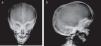

Presentation of the CaseA 4-year old male with a history of blindness in relation to congenital optic neuropathy of non-filiation aetiology and delayed growth. He presented at the emergency department after low intensity trauma in the right leg. An X-ray was taken which showed a fracture in the distal shaft of the tibia and fibula, together with a fracture callus in the proximal third of the fibula and general sclerosis of the visible bony structures which indicated sclerosing bone dysplasia (Fig. 1). The radiologic study was completed with a bone series, where a diffuse increase in bone density was highlighted with a “bone within bone” appearance and the enlargement of long bone metaphysis (Figs. 2–4). Radiologic findings determined the diagnosis of osteopetrosis.